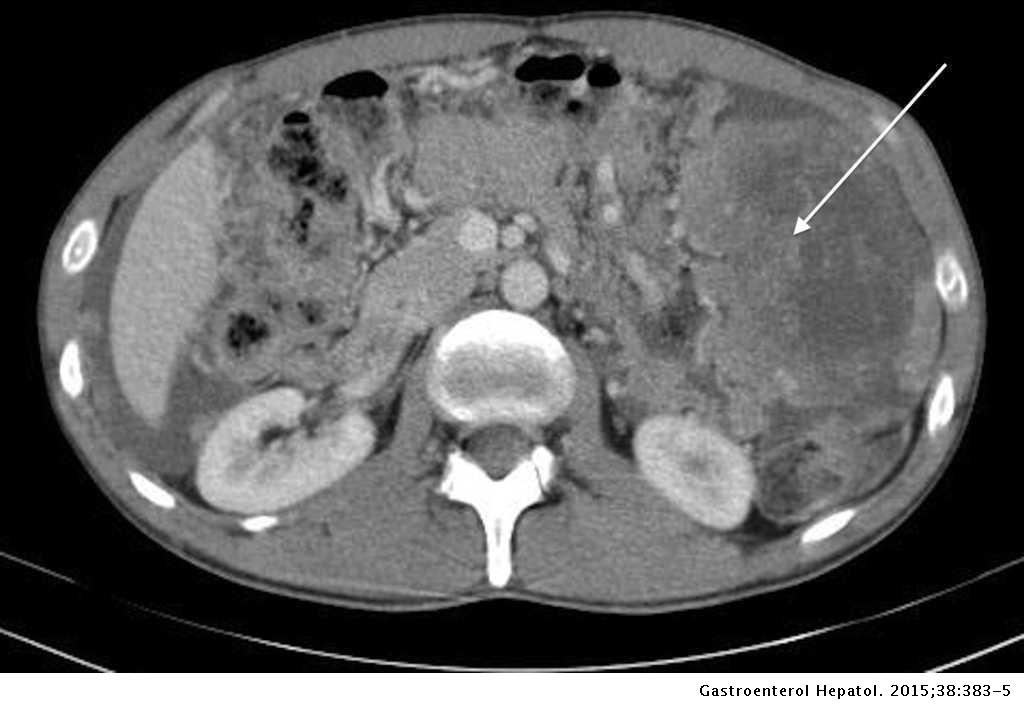

Los estudios radiológicos mostraron una masa voluminosa ubicada en el hipocondrio izquierdo acompañada de tumores de menor tamaño en la cavidad peritoneal y ascitis.

Previamente, el paciente se había realizado una biopsia por punción que reportó únicamente tejido necrótico, así como una tomografía computarizada de tórax y abdomen donde se evidenció una masa a nivel de hipocondrio izquierdo multilobulada que comprime estómago, desplaza bazo y se extiende hasta hipocondrio derecho comprimiendo la vía biliar; se reportan, además, varios tumores intraabdominales y ascitis. El paciente había sido atendido previamente en otra institución donde le colocaron un stent en vías biliares.